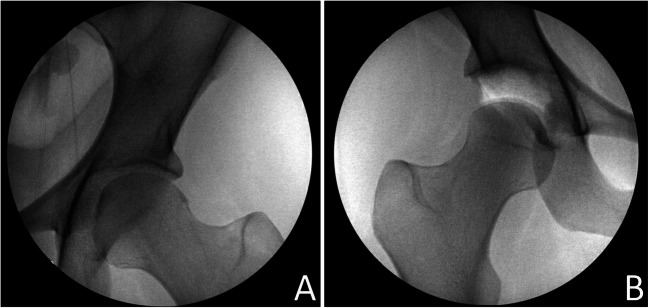

There are several physical examination maneuvers aimed at evaluating hip stability (Table 2). A clinically based axial distraction test and an intra-operative axial stress exam under anesthesia (Fig. 4) are the preferred physical examination maneuvers of the senior author to assess for post-surgical capsular instability. The clinically based axial distraction test is performed with the patient positioned supine on the examination table with the affected hip flexed to 45°, the knee flexed to 90°, and the contralateral leg relaxed in a neutral position. The examiner places their knee against the patient’s ischium to stabilize the pelvis while applying an axial force through the hip with the examiner’s hand placed on the proximal leg. Pain, apprehension, objective hip toggling, and asymmetry compared to the contralateral hip are the four major components assessed while axial distraction is applied. Pain is subjectively reported by the patient; apprehension is assessed by observing for anxiety or resistance to distraction; toggling is felt by the examiner as hip joint subluxation; and asymmetry is assessed by repeating the examination on the contralateral hip joint and comparing the axial distractibility between both hips. In the cohort of 31 patients studied by O’Neill et al. who were all easily distractable with gentle traction under anesthesia, 24 (77%) had at least 1 positive finding of pain, apprehension, or toggle on axial distraction testing [11].

Fig. 4.

Fluoroscopic images of an intra-operative axial stress exam under anesthesia in a patient undergoing right-sided revision hip arthroscopy. A Non-operative, asymptomatic left hip showing no joint space widening at 100 lbs of axial traction. B Symptomatic right hip showing significant joint space widening at 100 lbs of axial traction